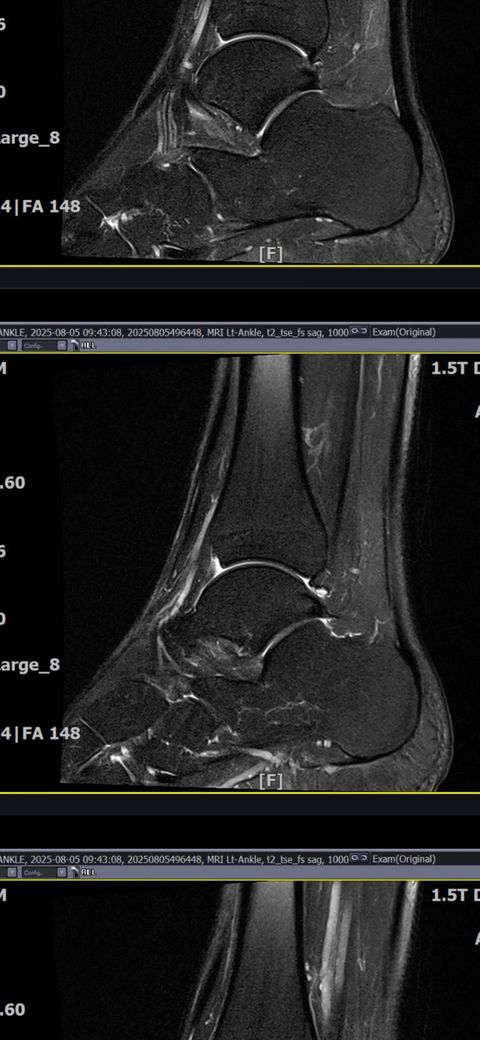

발목인대 상태 질문드립니다. (mri사진 첨부)

그래도 통증이 남아 8월 5일에 MRI를 촬영했는데, 병원에서는 “인대는 이어져 있고, 이 정도면 재활운동으로 호전될 것”이라는 설명을 들었습니다.

MRI 상 전거비인대와 발목 상태가 정말 회복 단계인지, 아니면 만성으로 넘어가는 건 아닌지 전문가분들의

의견을 듣고 싶습니다.

• 3번 째 사진

올려주신 mri를 보면 전거비인대는 연속성이 유지되고 있고 파열이나 큰 손상 흔적은 없어 재활로 회복 가능한 상태로 보입니다 다만 3개월 가까이 활동 시 통증과 미열감이 남아 있는 것은 조직 회복이 아직 완전히 끝나지 않았거나 주변 연부조직 관절 움직임 제한 등으로 인한 과민 반응일 수 있습니다.

초음파와 비교하면 mri 상으로 인대 연속성이 확인되므로 심각한 악화나 재파열은 아닌 것으로 판단됩니다

MRI상에서는 인대의 회복이 이루어지고 있는 덧으로 보이지만 인대의 회복은 소요되는 시간이 오래 걸리고, 주변 근육의 약화나 기능 저하로 인해 통증이나 불편감이 지속될 수 있습니다.